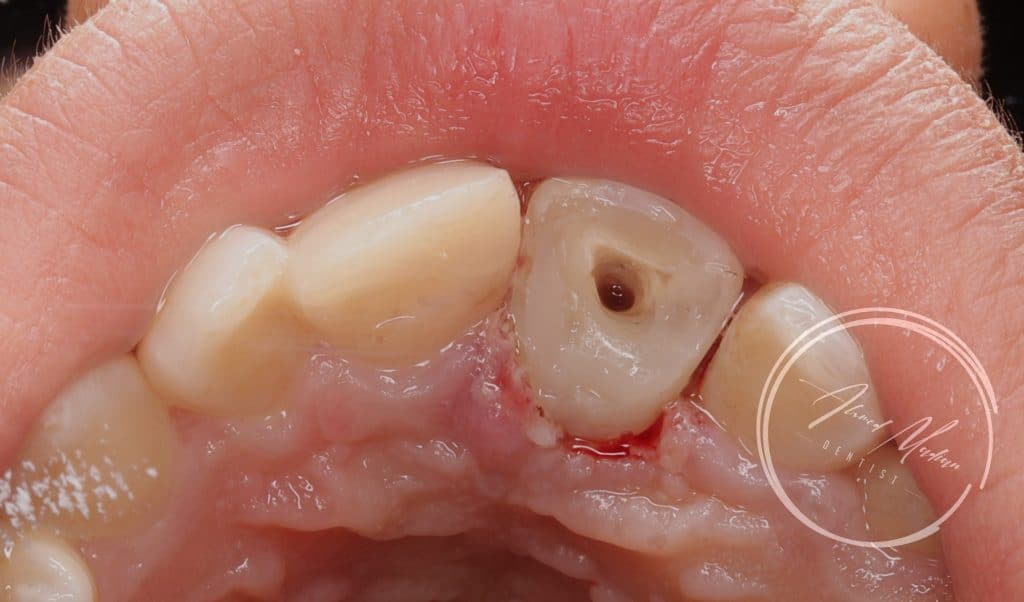

14 y male patient came to the office complaining of trauma in the anterior region

After clinical and radiographic examination , senstivity , mobility assessment

Tooth no 11 showed complicated crown root fracture , exposed pulp , closed apex

Tooth no 12 uncomplicated corwn fracture , class lV